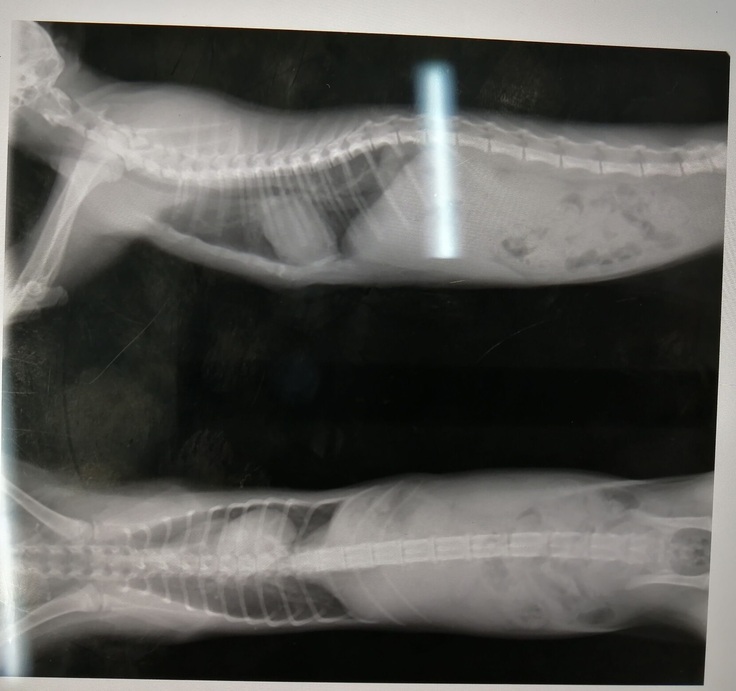

レントゲン検査もしました。

胸骨は、とってもきれいになりました!

先生にも、「普通の猫ちゃんと変わらないくらいになった」と言ってもらえましたよ^^

心臓の位置は相変わらず右に偏っていて右の肺を圧迫していますが・・・

漏斗胸の治療はひとまずここで終了とのことです!

ただ、胸骨は明らかによくなりました!

あとは胸骨に合わせて肋骨が開いてくれることを期待します。